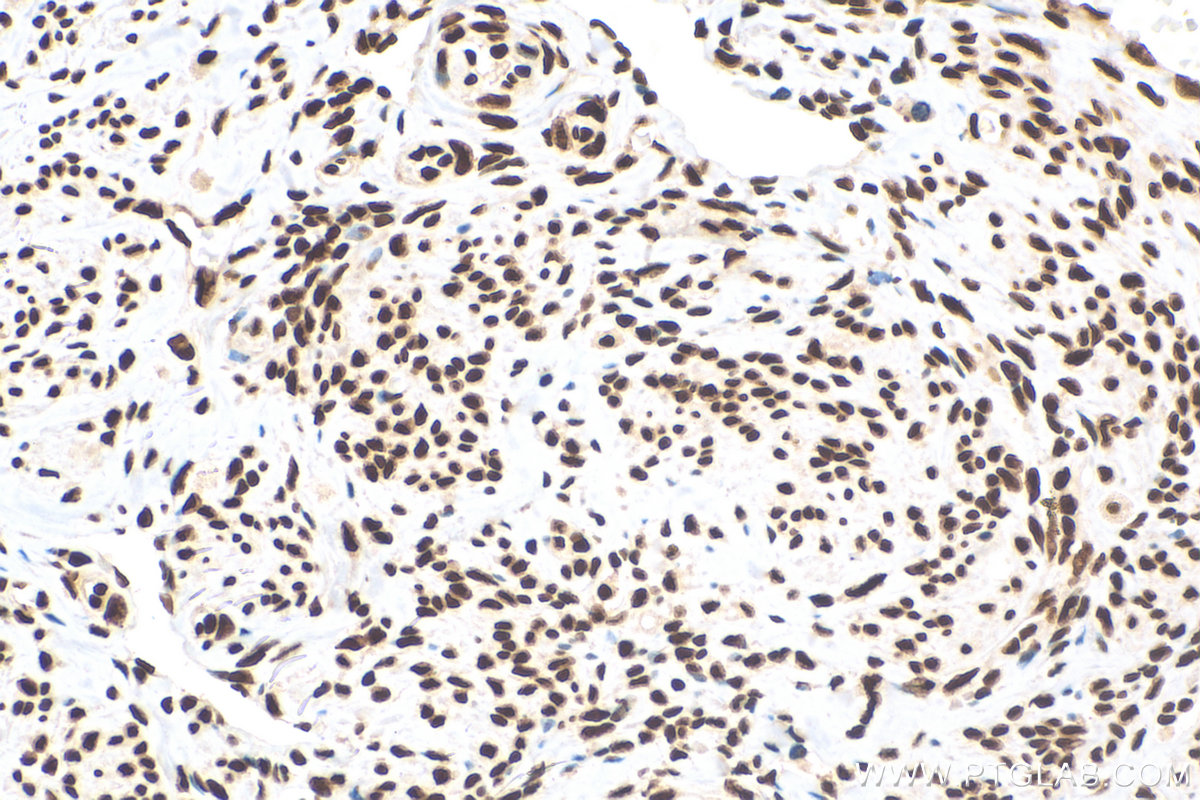

| Positive IHC detected in | human cervical cancer tissue Note: suggested antigen retrieval with TE buffer pH 9.0; (*) Alternatively, antigen retrieval may be performed with citrate buffer pH 6.0 |

| Immunohistochemistry (IHC) | IHC : 1:500-1:2000 |

68236-1-Ig targets HNRNPD in WB, IHC, IF/ICC, ELISA applications and shows reactivity with Human, mouse, rat, pig, rabbit samples.